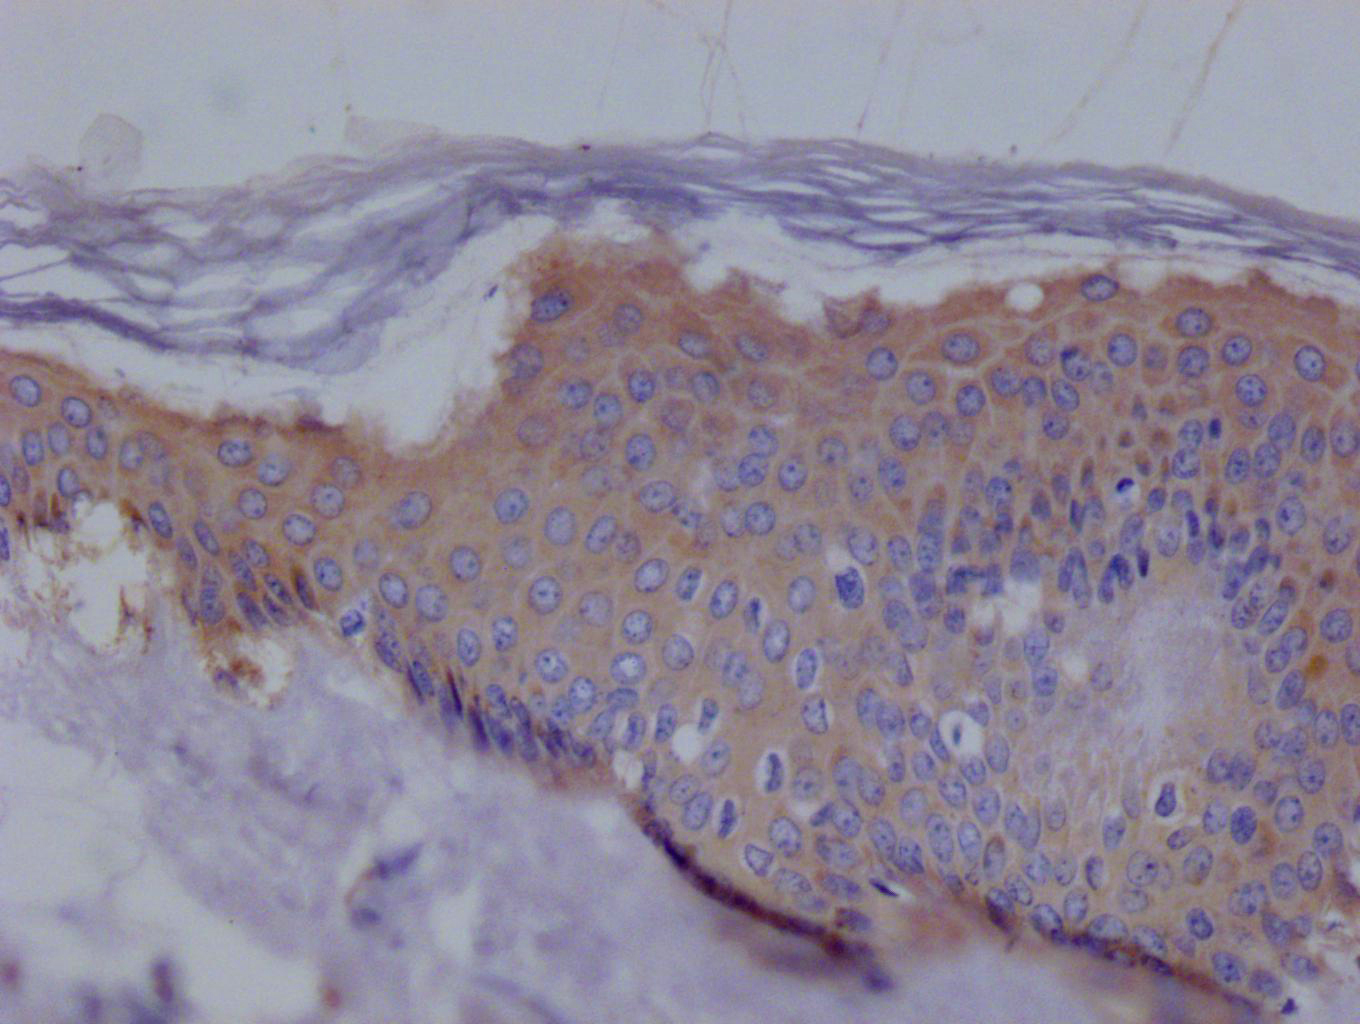

• IHC image of CSB-RA194531A0HU diluted at 1:100 and staining in paraffin-embedded human skin tissue performed on a Leica BondTM system. After dewaxing and hydration, antigen retrieval was mediated by high pressure in a citrate buffer (pH 6.0). Section was blocked with 10% normal goat serum 30min at RT. Then primary antibody (1% BSA) was incubated at 4°C overnight. The primary is detected by a Goat anti-rabbit polymer IgG labeled by HRP and visualized using 0.05% DAB.

CSB-RA194531A0HU為EZR重組單克隆抗體,靶向人源ezrin蛋白(EZR)。EZR是ERM蛋白家族成員,通過連接細(xì)胞膜與細(xì)胞骨架調(diào)控細(xì)胞形態(tài)、黏附和遷移,在腫瘤發(fā)生、轉(zhuǎn)移及上皮-間質(zhì)轉(zhuǎn)化(EMT)過程中發(fā)揮重要作用。該抗體經(jīng)ELISA和免疫組化(IHC)嚴(yán)格驗(yàn)證,適用于石蠟包埋組織切片檢測,推薦稀釋比例為1:50-1:200。實(shí)驗(yàn)數(shù)據(jù)顯示,其能特異性識別EZR抗原表位,在IHC應(yīng)用中呈現(xiàn)清晰的膜/細(xì)胞質(zhì)定位信號且背景干擾低,批次間一致性優(yōu)異。適用于癌癥生物學(xué)研究(如乳腺癌、結(jié)腸癌的侵襲轉(zhuǎn)移機(jī)制)、細(xì)胞極性調(diào)控分析及發(fā)育生物學(xué)相關(guān)實(shí)驗(yàn),支持通過IHC觀察腫瘤微環(huán)境中EZR蛋白分布特征,或結(jié)合ELISA技術(shù)定量檢測體外培養(yǎng)樣本中EZR表達(dá)水平。本產(chǎn)品采用重組表達(dá)技術(shù)制備,具備高靈敏度和穩(wěn)定性,為探究EZR在細(xì)胞信號傳導(dǎo)和疾病發(fā)生中的功能提供可靠工具。

Application Recommended Dilution

IHC 1:50-1:200